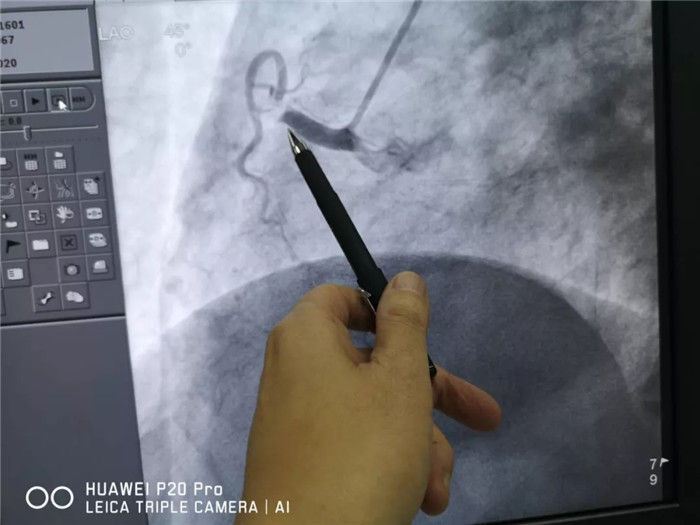

西藏阜康医院内三(心内)科值班医生迅速查体检查,诊断“冠心病-急性心肌梗死(下壁)”。急行冠状动脉造影检查结果显示:心脏冠状动脉急性闭塞病变。

术前影像